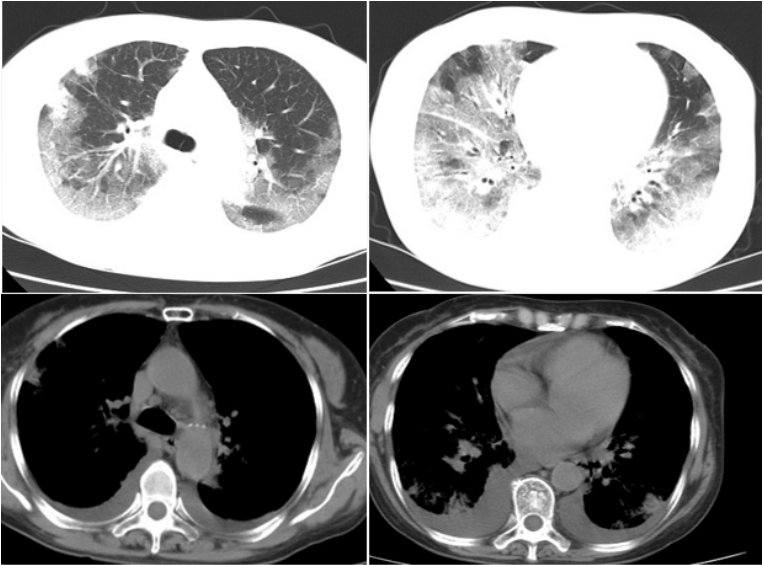

影像学:8月22日胸部CT见少量渗出(图1)。8月31日复查胸部CT可见大量弥漫渗出(图2),病情进展迅速。

图片

图1  患者胸部CT(2020-08-22)

图2  患者胸部CT(2020-08-31)

9月1日复查胸部CT可见肺部病灶较前明显改善(图3)

图3 患者胸部CT(2020-09-14)